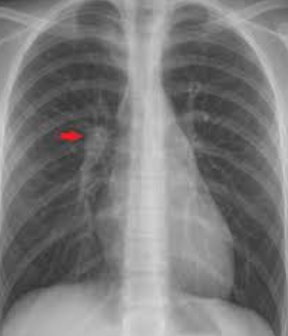

Q

Señora Tijuana, trabaja en una granja de leche bronca. Presenta tos titica. Tuberculina > 5, siguiente cuadro RX.

¿que tinción usara patología para confirmar el dx?

A

Nódulo de góhn

TINCIÓN - ZIEHL NIELSEN

TB

*langhans